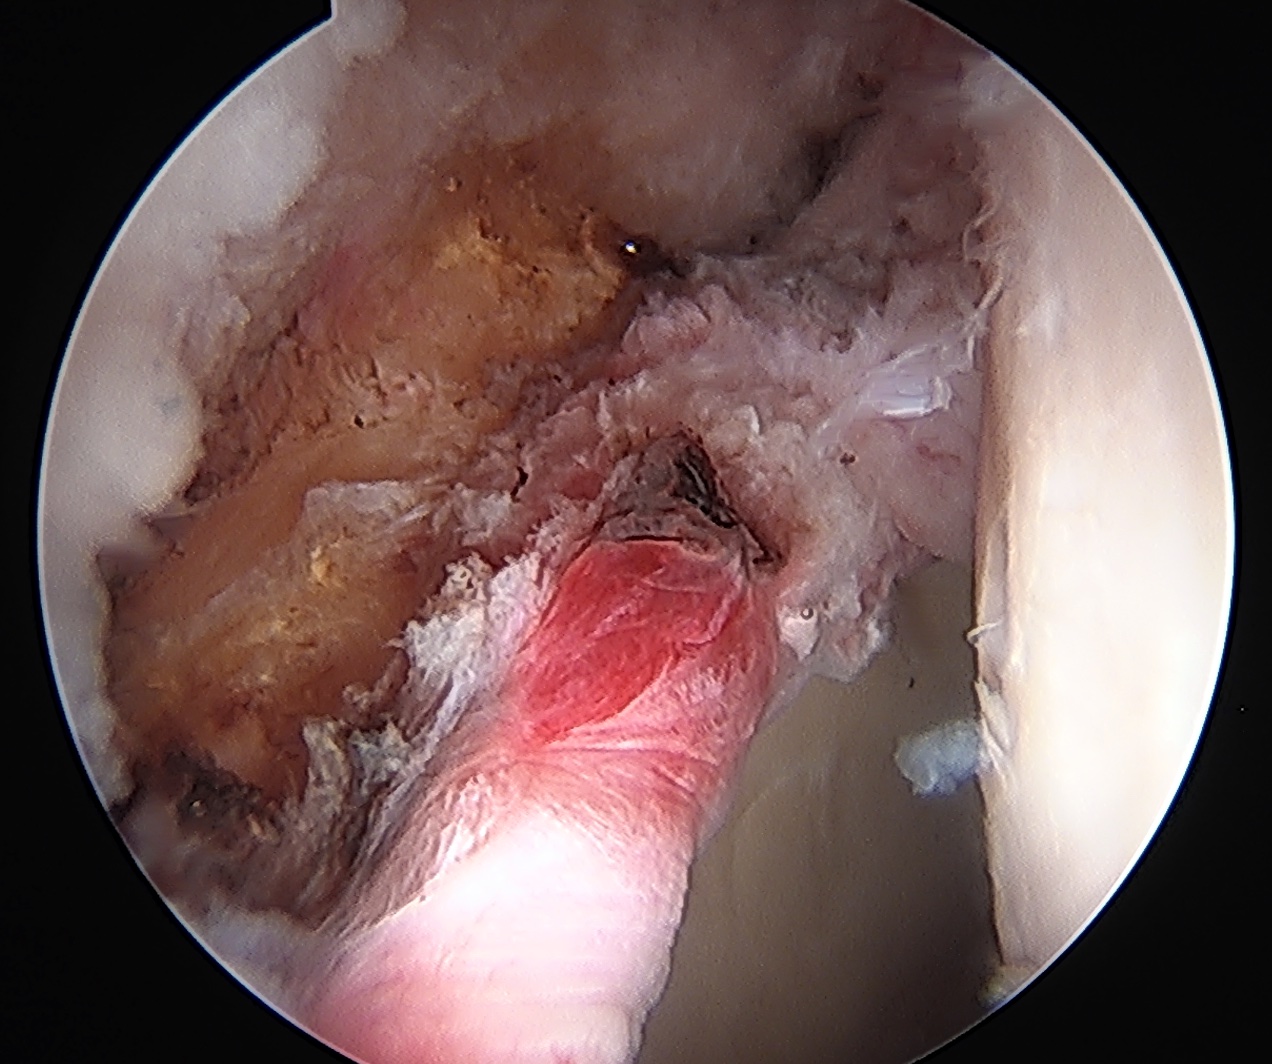

Heterotopic ossification - 1%

Heterotopic ossification anterior capsule

Capsular retear / deficiency

- may cause microinstability / pain

- most studies point towards superior outcomes with capsular repair

Anterior capsular deficiency on MRA post hip arthroscopy